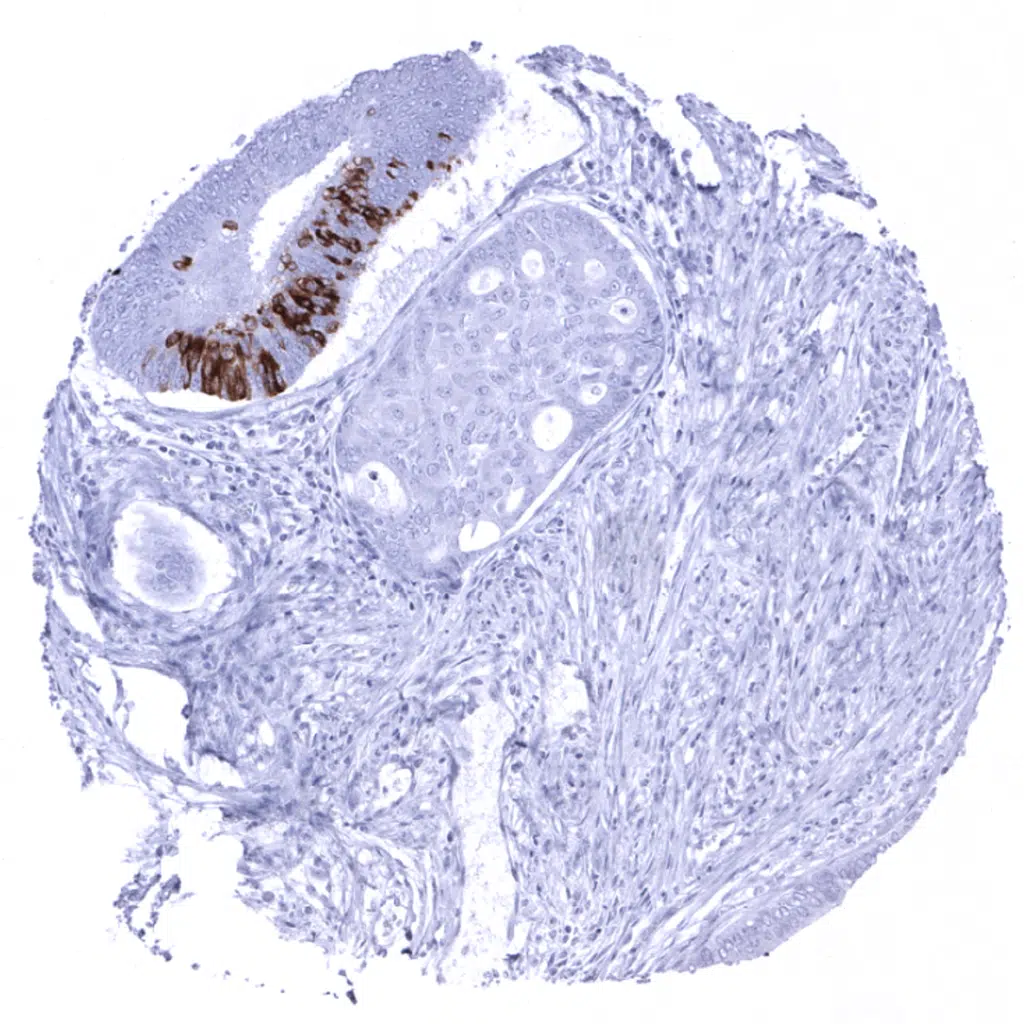

Colon- MUC5AC negative colorectal adenocarcinoma